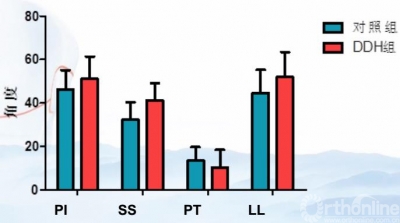

图3 DDH组与对照组骨盆角度对比

结果发现,骨盆从仰卧位到站立位,PSSC减小,骨盆后倾,髋臼前倾角增大,髋臼前覆盖减小。而对于DDH患者,为消除前侧不稳定,骨盆会发生代偿性前倾。因此DDH患者站立位时骨盆较正常人前倾增大。